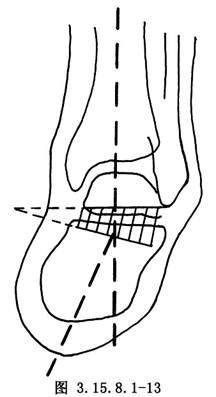

6.5.3 3.截骨矫形

先用骨刀截除跟骰关节和距舟关节,楔形截骨基底在背外侧纠正内翻畸形(图3.15.8.1-8),切除角度等于X线片第2趾和足中线形成的角度(图3.15.8.1-9)。若纠正足外翻畸形,楔形截骨基底可设计在内侧(图3.15.8.1-10),由于距舟关节和跟骰关节在一个平面上,切除角度是一致的(图3.15.8.1-11)。最后切除距下关节,纠正跟骨内收(图3.15.8.1-12),根据X线片胫骨中线和跟骨中线形成的角度,做外侧楔形切除(图3.15.8.1-13)。当骨刀切到对侧时,注意轻缓,尤其纠正外翻时,更要注意防止误伤胫后的血管及神经(图3.15.8.1-14)。将已切除的骨面合拢,如畸形纠正,骨面能紧密对合(图3.15.8.1-15),周围空隙植入切除多余的松质骨。